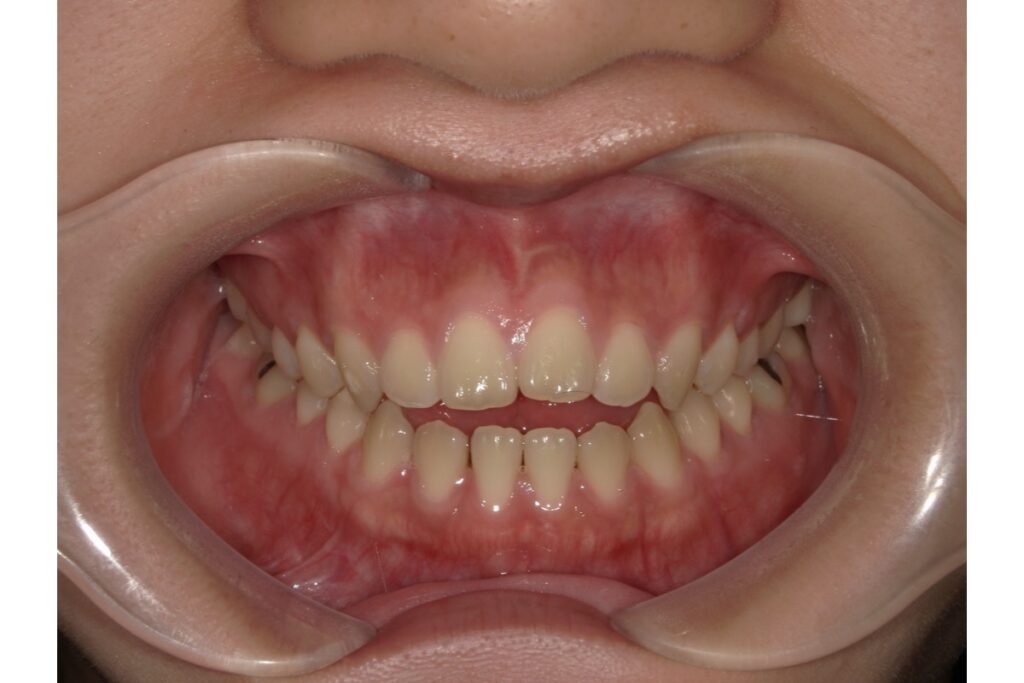

具体的にどんな歯並びの問題が起こるのか?

頬杖を続けることで起こる歯並びのトラブルには、以下のようなものがあります。

・出っ歯(上顎前突)

頬杖によって下顎が後ろに押し込まれると、上の前歯が強調されて前に出ているように見える、いわゆる「出っ歯」になりやすくなります。

・受け口(下顎前突)

逆に、下顎を前に押し出すような頬杖をする場合には、下の歯が前に出て「受け口」になる可能性があります。

・開咬(かいこう)

前歯が噛み合わず、上下に隙間ができる状態。頬杖による筋肉や骨格のバランスの崩れが、開咬の一因になることもあります。

・叢生(歯のガタガタ)

圧力の影響で歯の生えるスペースが狭くなり、結果的に歯が重なり合って「ガタガタ」になる叢生(そうせい)も、頬杖が関与しているケースがあります。